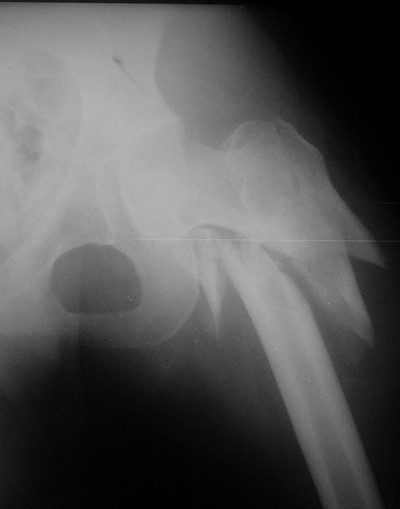

В середине декабря был наложен спицестержневой аппарат, с помощью которого к сегодняшнему удалось устранить укорочение бедра (рис. 2). В течение последних 4-х дней устраняем смещение дистального отломка бедренной кости по ширине. Раны на передней брюшной стенке почти зажили. Температура тела и лабораторные показатели нормальные. Планируем выполнить закрытый остеосинтез левой бедренной кости  удлиненным проксимальным бедренным штифтом производства фирмы "Остеомед".

Нас смущает, что малый вертел бедренной кости остается значительно смещенным проксимально и кнутри.

Как вы думаете, насколько это повлияет на функцию конечности в последующем?  И еще, интересно, кто-нибудь из участников форума в подобных ситуациях делал ли открытую репозицию и фиксацию малого вертела?